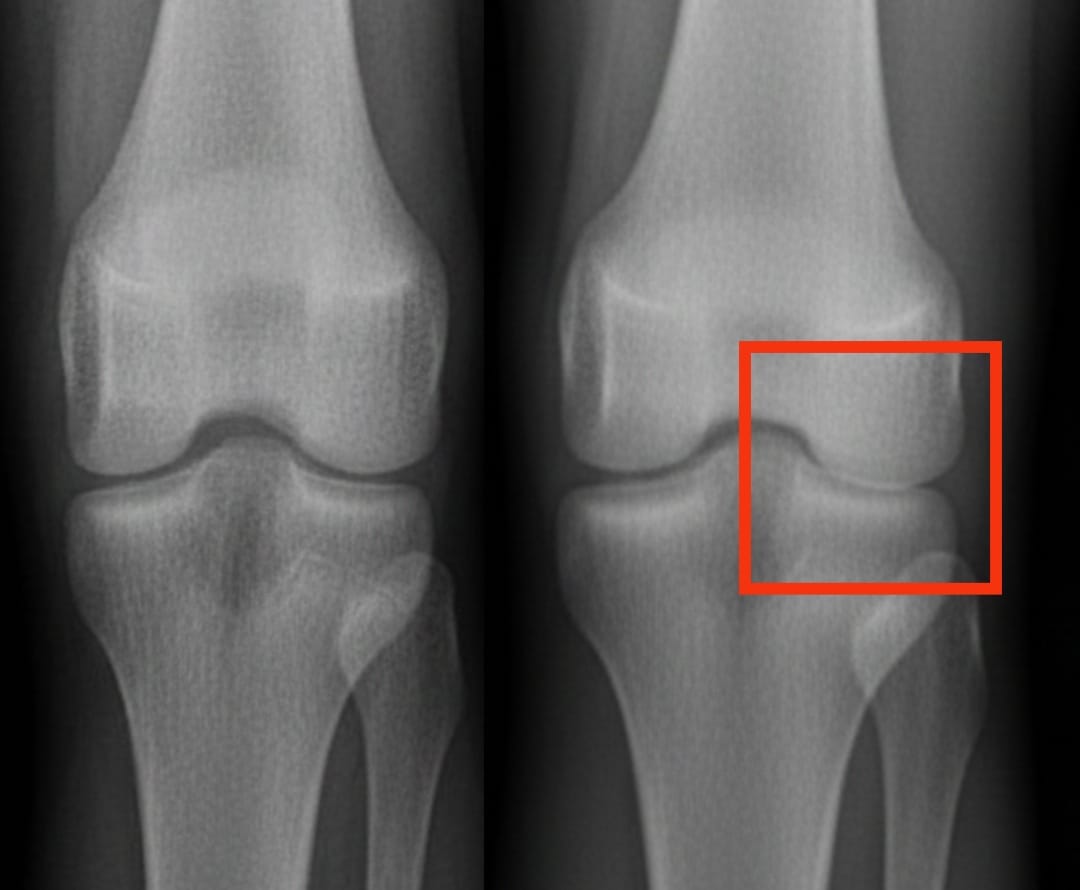

La artrosis de rodilla afecta a cientos de millones de personas en todo el mundo. Se caracteriza por un desgaste progresivo del cartílago, lo que provoca dolor y dificultades para moverse. Entre las soluciones propuestas, las inyecciones de plasma rico en plaquetas despiertan un interés creciente. Este tratamiento utiliza la propia sangre del paciente, concentrada en plaquetas, para estimular la reparación de los tejidos y reducir la inflamación.

Un análisis reciente comparó la eficacia del plasma rico en plaquetas con la de otras inyecciones comunes: el ácido hialurónico, los corticoides y un placebo salino. Los resultados muestran que el plasma rico en plaquetas mejora significativamente el dolor y la movilidad después de seis meses, con beneficios que persisten hasta un año. Estas mejoras son más marcadas que las obtenidas con el ácido hialurónico o los corticoides, y muy superiores a las del placebo.